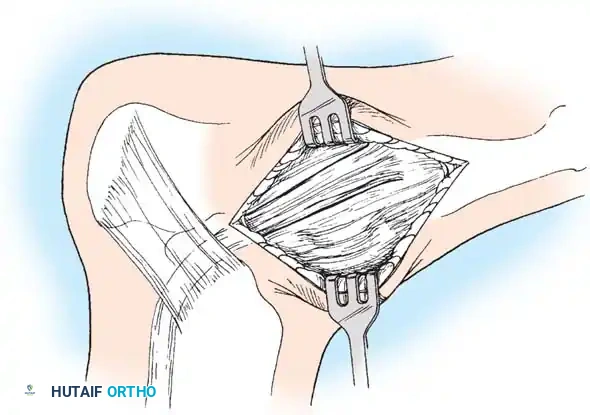

جراحة إزالة التحام العقب والزورقي

في حالة التحام العقب والزورقي، يعتبر الاستئصال الجراحي للجسر العظمي هو الخيار المفضل، خاصة لدى الأطفال والمراهقين الذين لا يعانون من خشونة في المفاصل.

يقوم الجراح بإزالة الجسر العظمي بالكامل لضمان عدم عودته. ولمنع تكوّن العظم مرة أخرى في نفس المكان، يتم وضع نسيج عازل في الفراغ الناتج، مثل جزء من عضلة مجاورة (Extensor digitorum brevis) أو نسيج دهني، أو استخدام الشمع الطبي. أثبتت الدراسات أن هذه الجراحة تنجح بنسبة عالية في تخفيف الألم واستعادة جزء كبير من حركة المفصل.